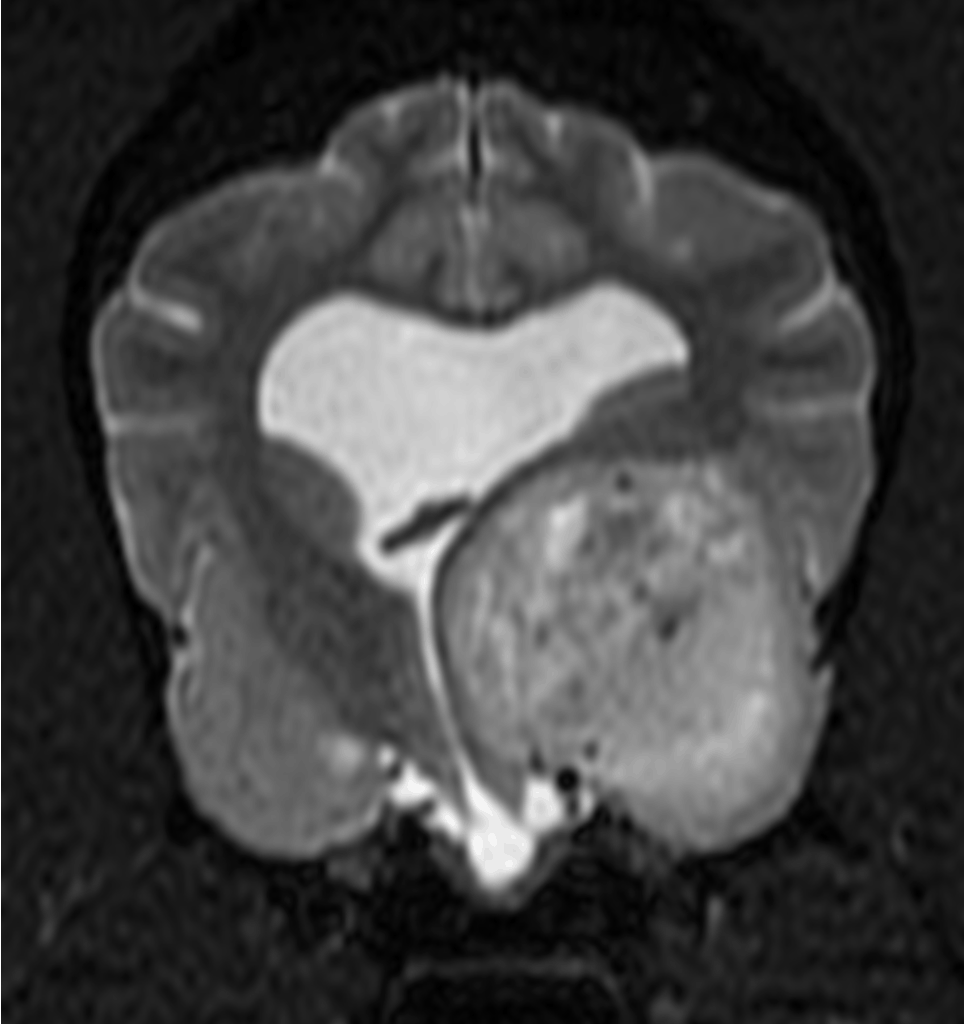

Magnetic Resonance Imaging

Magnetic resonance imaging (MRI) helps diagnose many medical conditions. MRI uses a powerful magnetic field, radiofrequency pulses and a computer to produce detailed images of organs, soft tissues, bones, vessels and virtually all other internal body structures. These detailed images allow radiologists to better evaluate and determine the presence of certain diseases that may not be assessed adequately with other imaging methods, including CT.

MR examinations help diagnose or monitor treatment for conditions such as:

- disease of the brain and spinal cord

- tumors of the chest, abdomen or pelvis

- certain types of heart disease

- blockages, enlargements or anatomical variants of blood vessels

- diseases of the liver and other abdominal organs

- diseases of the gastrointestinal tract

- cysts and solid tumors in the kidneys and other parts of the urinary tract

- tumors and other abnormalities of the reproductive organs